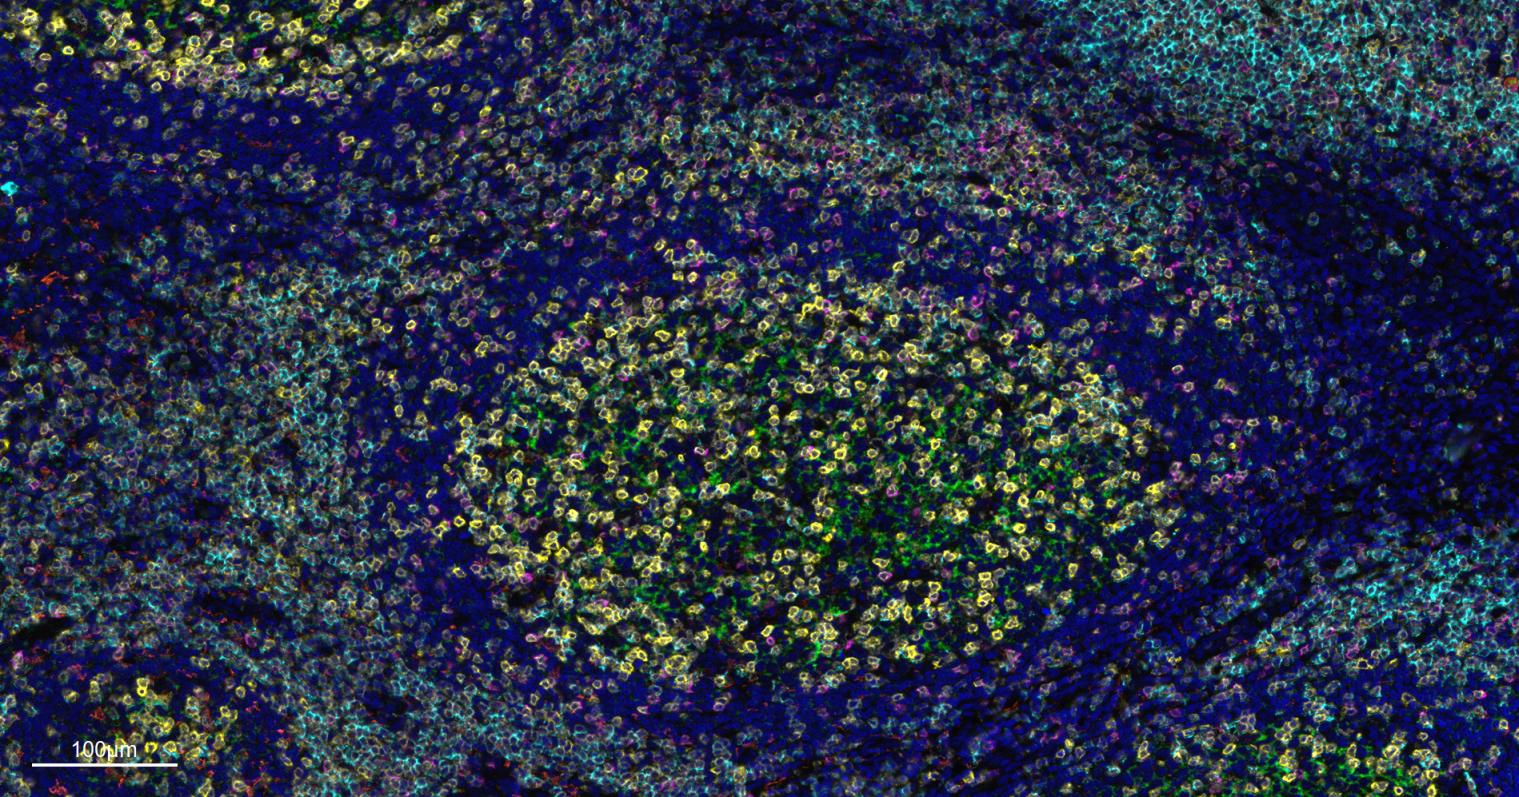

IHC-PHuman1:100-500

IHC-FHuman1:100-500

IFHuman1:100-500